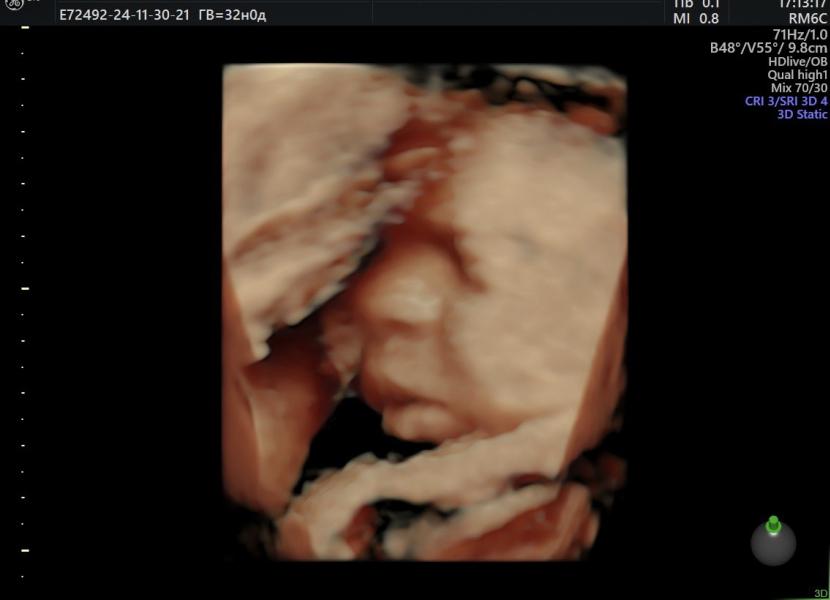

Сегодня прошел 3-й скрининг 🥰

Что мы имеем…😁

1)вторая дочка похоже будет пухляшка, уже 2кг вес

2) все хорошо, положение заняла правильное , развиваемся в срок 👌🏽👍🏼

Вторая дочь копия первой 😍 мы с мужем в один голос сказали, что они похожи, единственное вторая дочь пухленькая , первую я маленькую родила, всего 3кг